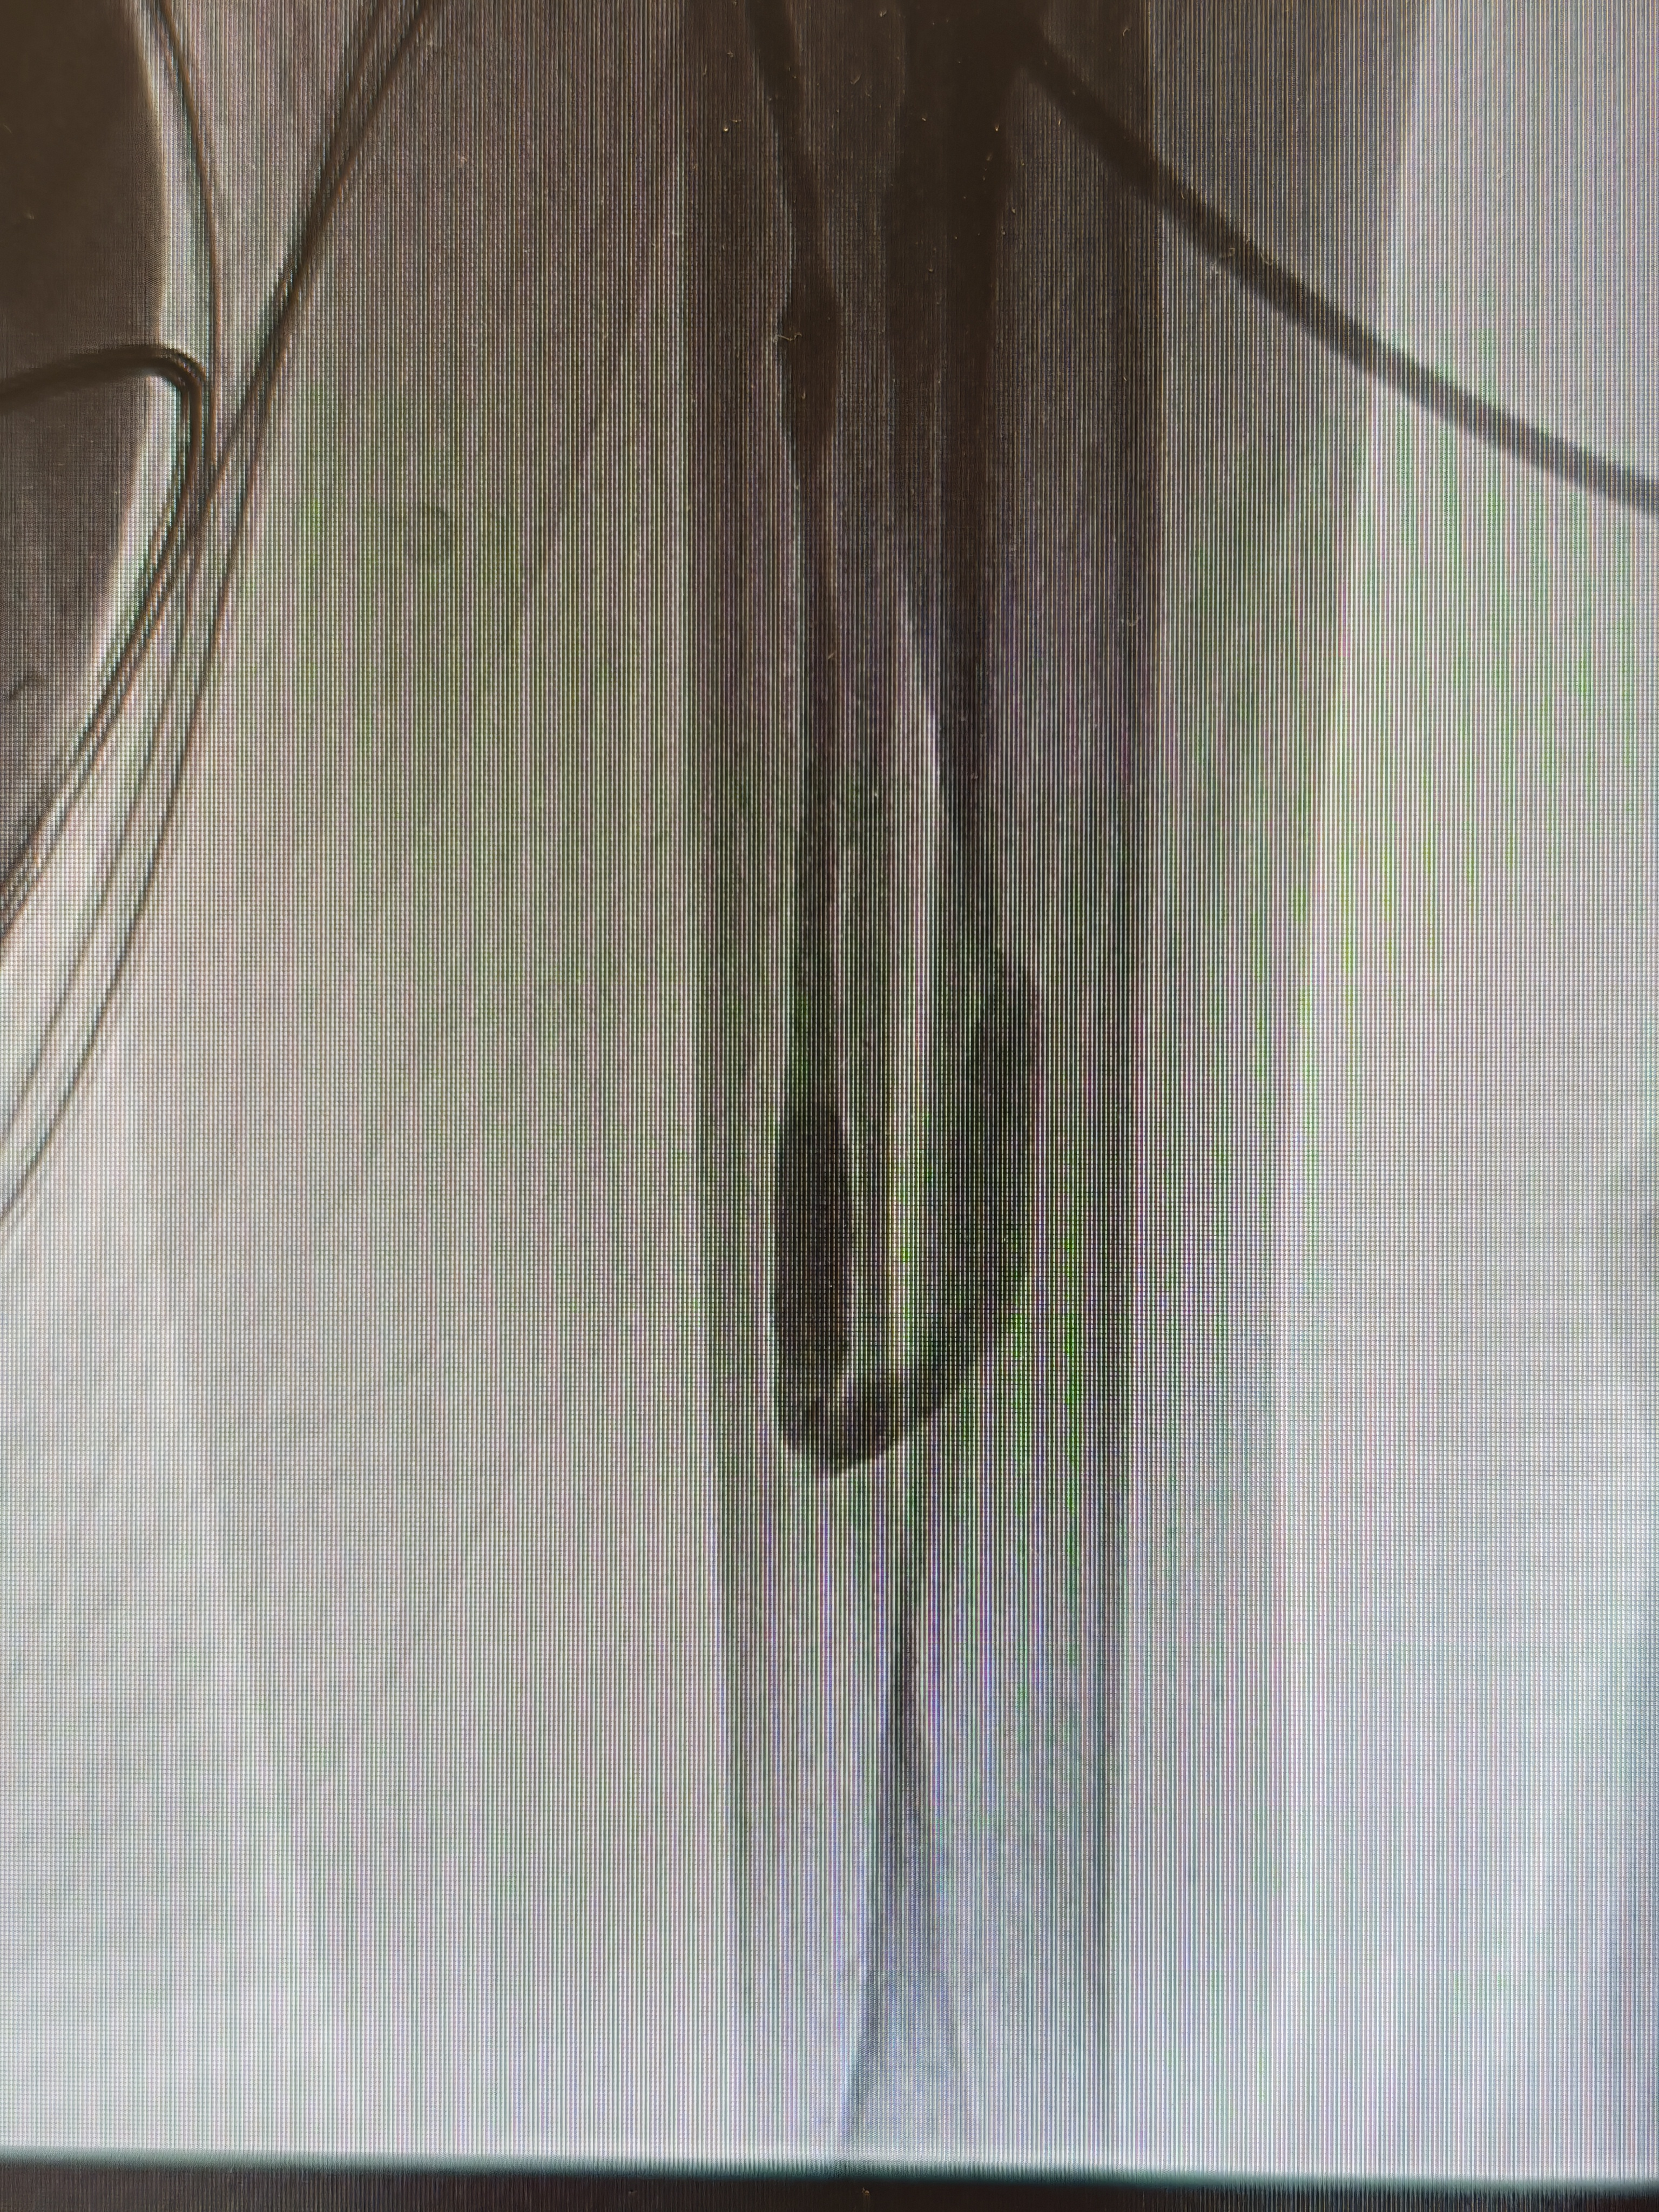

患者入院后,医院立即启动肾病血透通路 MDT 多学科会诊。四川泰康医院副院长、血管介入博士、血管通路专家郭伟昌牵头,为患者量身制定个体化手术方案。在充分术前准备下,郭伟昌副院长带领肾内科团队,为患者实施经肱动脉入路 DSA 下动静脉内瘘造影 + 球囊扩张 + 腔内溶栓术。术中造影显示,患者内瘘瘘口狭窄约 80% 并伴血栓形成。郭伟昌副院长精准操作,以 5 mm 高压球囊扩张病变,并予以尿激酶溶栓。术后复查造影显示,狭窄段完全开通,血流通畅。术后第二天,患者即可使用内瘘顺利透析,彩超复查血流量恢复至理想水平。